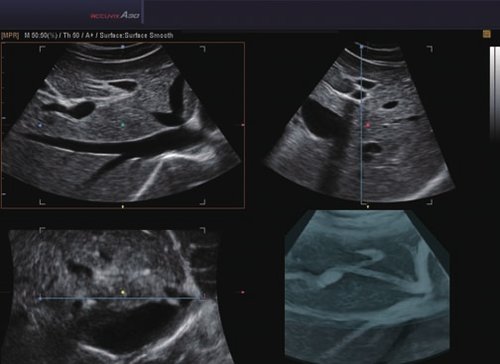

Das Samsung Accuvix A30 ist ein hochwertiges Ultraschallsystem, das mit seiner 3D-Technologie herausragende Ergebnisse ermöglicht. Das Sonographiegerät besitzt 5 Sondenanschlüsse und ist mit 20 unterschiedlichen Schallköpfen kompatibel. Mit dem A30 können Schallköpfe vom Typ Konvex, Mikrokonvex, 3D-Konvex, CW, Phased Array, Linear und Endokavitär verwendet werden. Bei zwei der Sonden handelt es sich um S-VUE Ultraschallsonden, die durch ihre höhere Bandbreite noch feinere Scans erzeugen.

Das Ultraschallsystem hebt sich besonders durch seine 3D-Technologie wie die Face Auto Detection für detaillierte Ultraschallbilder von Föten oder das Volume Shade Imaging, das sich auf die lebensnahe Darstellung von Schattierungen und Hauttönen fokussiert, ab. Mit weiteren wertvollen Technologien wie dem ElastoScan™ werden Tumore schneller erfasst und durch die HD Volumen Bildgebung sowie das DMR+™ eine erstklassige Bildqualität erzielt.

• 3D-Bildmodus

• 4D-Bildmodus.

• FAD™, die Face Auto Detection, stellt das Gesicht eines Fötus besonders detailliert dar. Überflüssige Daten werden entfernt und ein besonders realistisches Bild gezeichnet.

• Volume Shade Imaging, kurz VSI™, visualisiert ein 3D-Bild, das Hauttöne und Schattierungen auf ein qualitativ neues Niveau hebt.

• Die HD Volumen Bildgebung reduziert unerwünschte Streumuster und sorgt für eine präzisere Darstellung der Bilder.